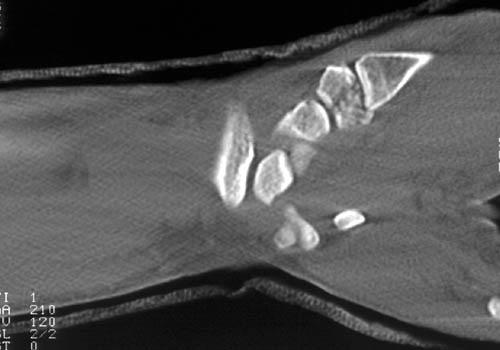

Identification of carpal fractures other than the scaphoid can be difficult on conventional radiographs. The second most frequently fractured carpal bone is the triquetrum. Types of fractures include the dorsal cortex, volar cortex and triquetral body. Body fractures usually occur in conjunction with other carpal fractures and ligamentous injury to the wrist. The fracture of the dorsal cortex can be identified as an avulsion fragment on the lateral radiograph. This type of fracture usually follows a fall on the dorsiflexed wrist or avulsion by the radiotriquetral and scaphotriquetral ligaments, which insert on the dorsal surface of the triquetral bone. Avulsion fractures can also arise from the volar surface of the bone. This type of fracture is not readily identified on the three radiographic views of the wrist, but requires an instability series, CT or MR to detect. Unfortunately. this subtle fracture is associated with injury to the perilunate ligaments resulting in lunatotriquetral instability and long term pain and carpal dysfunction. If this type of fracture is identified, correlative imaging should be performed with MR respectively, to evaluate the perilunate ligaments.

Fractures of the hamate most commonly involve the hamate hook. This type of injury is usually caused by direct trauma by swinging the handle of a baseball bat, golf club or tennis racquet, but can infrequently result from trauma directed to the proximal palm. Traditional radiographic views of the wrist are usually insufficient to identify this fracture. Carpal tunnel radiographs or supinated oblique views of the wrist are required; however, even these views may not demonstrate the fracture, necessitating CT. CT in the axial plane is best for evaluation of the hamate hook. Sagittal displays are better for the body of the hamate. Diagnosis is important because the ulnar nerve travels near the hamate hook, and neurologic damage can result from the motion of an ununited fracture.